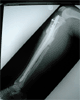

Tibia deformity-post lengthening on 14 years old chinese girl

Pre

Op